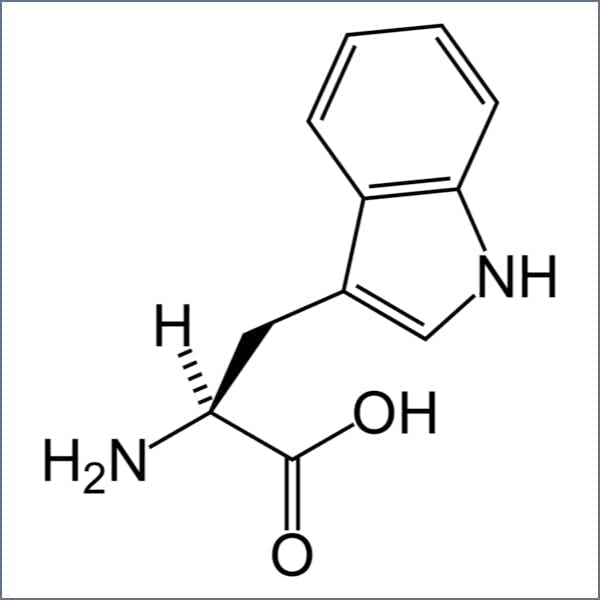

L-Tryptophan#

Tryptophan is known as a natural sedative but is also a precursor to serotonin. It’s essential for our feelings of contentment. It also helps regulate appetite, mood, sleep, and our response to pain.9